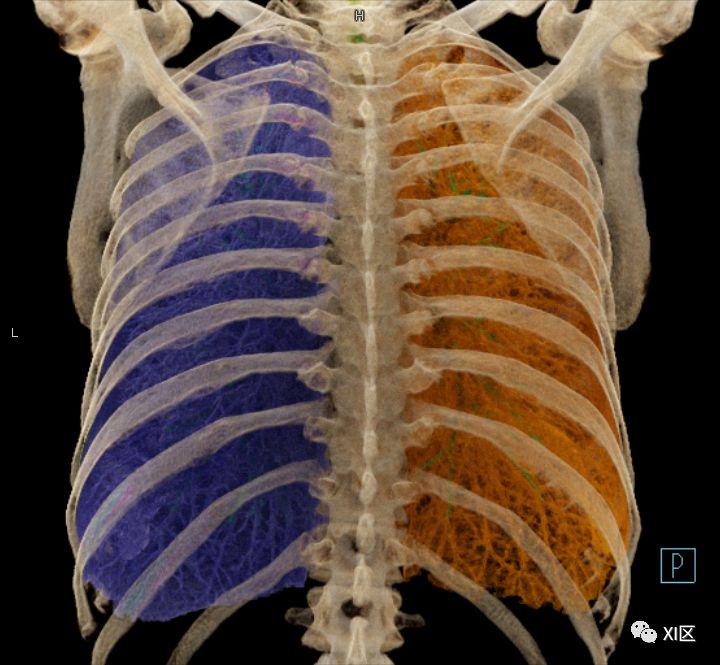

前后位,双侧位,后前位显示气道肺与胸部骨骼的关系

左肺借斜裂成上、下两叶;右肺借斜裂和水平裂成上、中和下叶三叶。